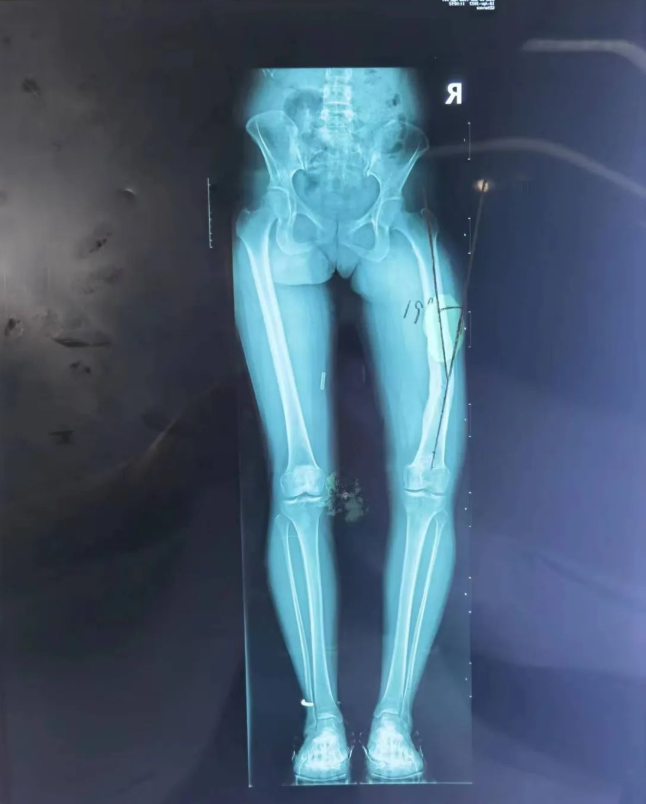

经接诊医师崔家平检查发现,患者右股骨畸形并功能障碍,右膝关节僵硬,不能活动;影像检查后发现右下肢前后及内外成角畸形明显,测量发现右侧股骨前后成角30度,内外成角19度,患者及家属急盼迅速治疗以缓解疼痛、矫正畸形。

(术前检查影像)